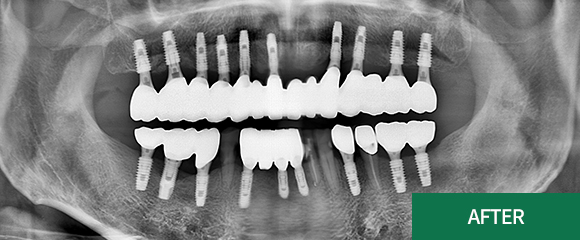

전악(전체) 임플란트

CASE 2